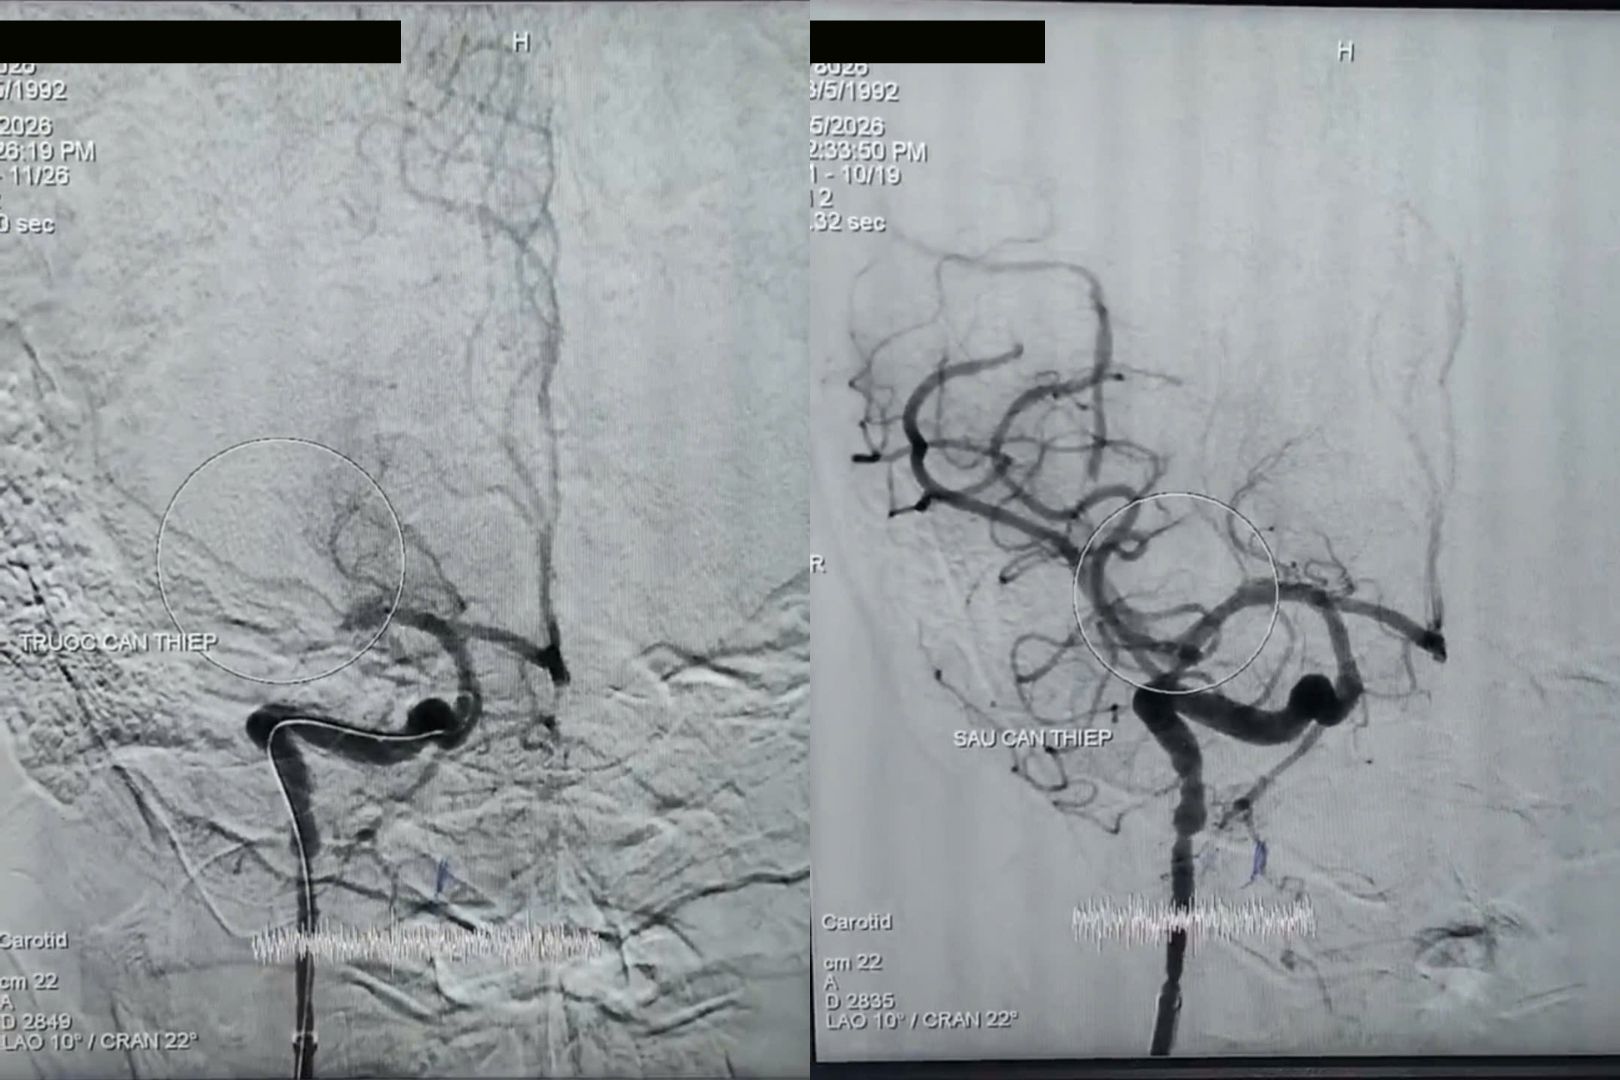

Trước tình trạng nguy kịch của bệnh nhân, ê kíp bác sĩ Khoa Thần kinh Đột quỵ đã quyết định tiến hành can thiệp lấy huyết khối cấp cứu nhằm tái thông mạch máu não.

Thủ thuật can thiệp đã lấy ra cục huyết khối gây tắc mạch và tái thông hoàn toàn dòng chảy, đạt mức TICI 3.